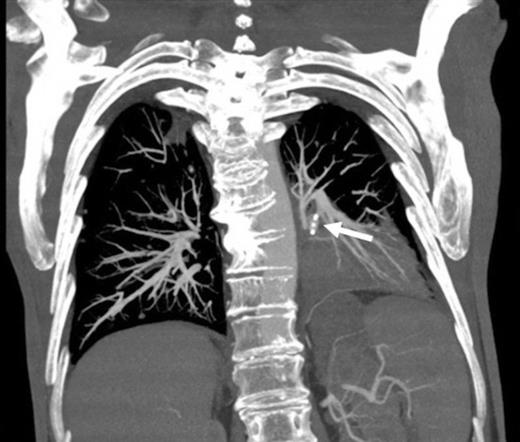

Left pulmonary artery digital subtraction angiography image demonstrating filling of left lower lobe aneurysm (arrow)

Digital subtraction angiography post deployment of the AVP 4 device in the PA branch feeding the aneurysm (arrow). No residual or collateral filling seen